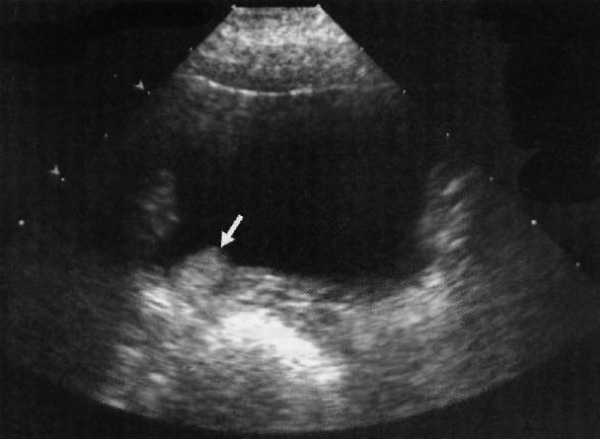

Мультикистоз почек является наиболее распространенной причиной развития объемных образований у младенцев. Диспластический мультикистоз почек может поражать только один сегмент почки или одну часть удвоенной почки, однако, чаще всего в патологический процесс вовлекается вся почка. Патология характеризуется образованием множественных не сообщающихся друг с другом кистозных структур разного размера. Наиболее распространенным вариантом является формирование наиболее крупных кист на периферии почки (фото 6). При этом артерия почки отсутствует или непроходима, мочеточник не сообщается с лоханкой, таким образом, почка не функционирует.

Фото 6. Мультикистоз почки. Продольное ультразвуковое изображение правой почки ребенка: наблюдаются множественные несообщающиеся между собой кисты